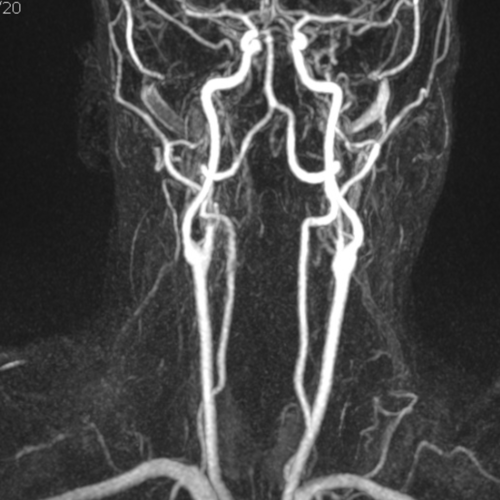

Cet examen est réalisé pour analyser les vaisseaux artériels du cou et du cerveau. Il est réalisé en dépistage de la maladie cardio vasculaire, en cas d’ AVC, de vertige, de trouble visuel.

Ces vaisseaux naissent de la crosse de l’aorte .

On distingue :

• Le Tronc Brachio-Céphalique (à droite)

L’artère subclavière droite (vers le bras droit).

L’artère carotide commune droite (vers la tête).

• L’Artère Carotide Commune Gauche

Elle naît directement de l’aorte. À la base du cou, elle se divise en deux :

Carotide interne : Elle monte directement nourrir le cerveau.

Carotide externe : Elle nourrit le visage et le cuir chevelu.

• L’Artère Subclavière Gauche

Elle part directement de l’aorte pour irriguer le bras gauche. Elle donne également naissance à l’artère vertébrale, qui passe dans les vertèbres du cou pour rejoindre l’arrière du cerveau.